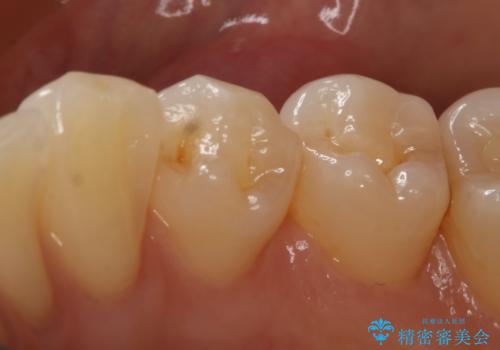

- 右下4番の虫歯治療を希望され来院された患者様です。

セラミックでの治療を希望されたため、切削量・形態を考慮しセラミックインレーでの治療を計画しました。

う蝕を除去した後、CRで裏層した上で形成、印象をしています。

装着時にはラバーダムを使用しています。